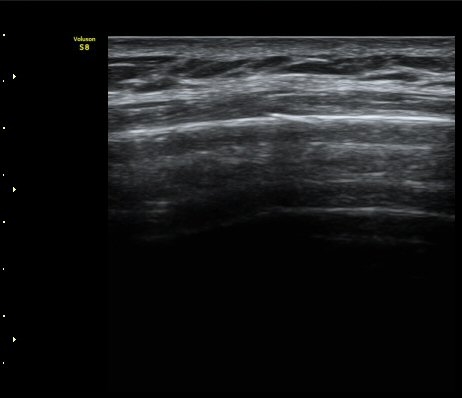

¹Ì¼¼ÇÏ°Ô °¥ºñ»À ÇÇÁú°ñ ¿¬°á¼º ¼Ò½ÇÀÌ °üÂûµÊ(loss of cortical continuity of rib)  »çÁø 1, 2

°¥ºñ»À ¹Ì¼¼°ñÀýÀÌ È®ÀÎ µÊ